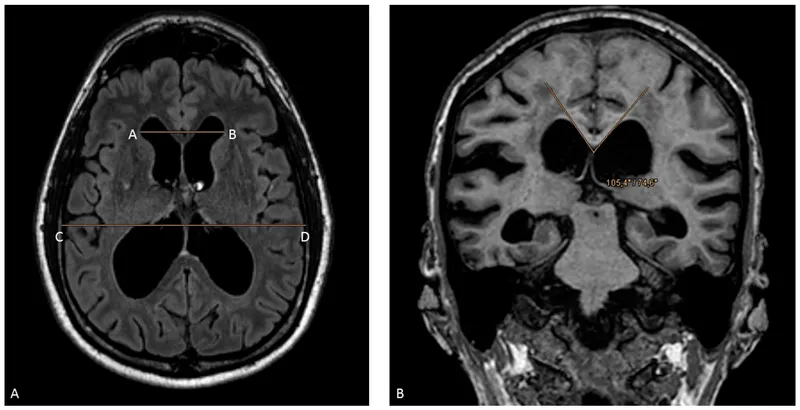

- For Normal Pressure Hydrocephalus (NPH), calculate the Evan's Index.

- Evan's Index > 0.3 is diagnostic for NPH.

- $Evan's\ Index = \frac{Maximal\ Frontal\ Horn\ Width}{Maximal\ Internal\ Skull\ Diameter}$

⭐ In NPH, ventriculomegaly is disproportionately large compared to sulcal effacement, distinguishing it from hydrocephalus ex vacuo (brain atrophy).